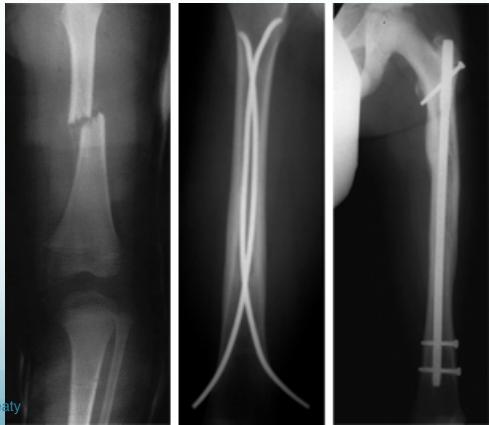

- IMN: Intramedullary nail / Locked(with screws)

- The treatment of choice

- Relative stability

- Allows early weight-bearing

Intramedullary Nailing

- IMN: Intramedullary nail

- Locked IMN (with screws)

http://www.synthes.com www.healio.com